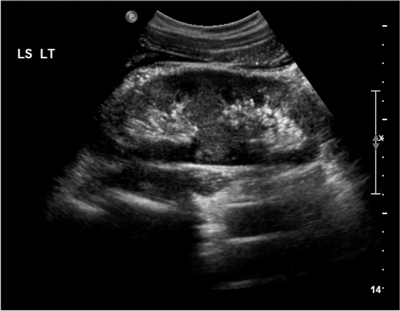

Figure 1a: US demonstrating poorly visualised lower pole.

On the plain abdomen film the lower poles of the kidneys are seen medial to the upper poles, in contrast with normal renal anatomy where lower poles are lateral. Ultrasound may reveal the isthmus lying anterior to the spine and contiguous with the lower poles of both kidneys. However due to the positioning of bowel gas centrally, the isthmus may not be clearly viewed and appearances may be of a curved configuration to the kidneys with poorly defined lower poles. In the longitudinal plane the kidneys may appear as an inverted triangular or pyriform shape [3,4]. Contrast enhanced CT will provide the clearest imaging, and helps to define the structural abnormalities of the horseshoe kidney. On CT the following questions can be answered: the degree and site of the fusion, degree of renal malrotation, any associated collecting system abnormalities, and any renal parenchymal changes. CT enables differentiation between normal and fibrous parenchyma within the isthmus, which is almost always functioning tissue.